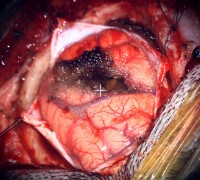

- Intra-op